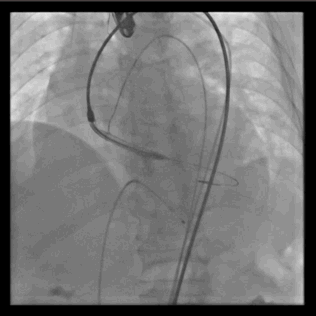

VenusA 26支架,高位 释放

1.ring释放到mark点往下2mm处,造影观察位置(此时仍可以调整位置)

2.瓣膜释放瓣架打开 瓣架开始附着在钙化区 高速起搏 血压下降 系统保持相对稳定

3.支架开始贴壁,血压开始恢复,支架下部锚定区固定,停止起搏 。

4.造影观察冠脉情况 瓣叶运动工作 是否PVL 返流等